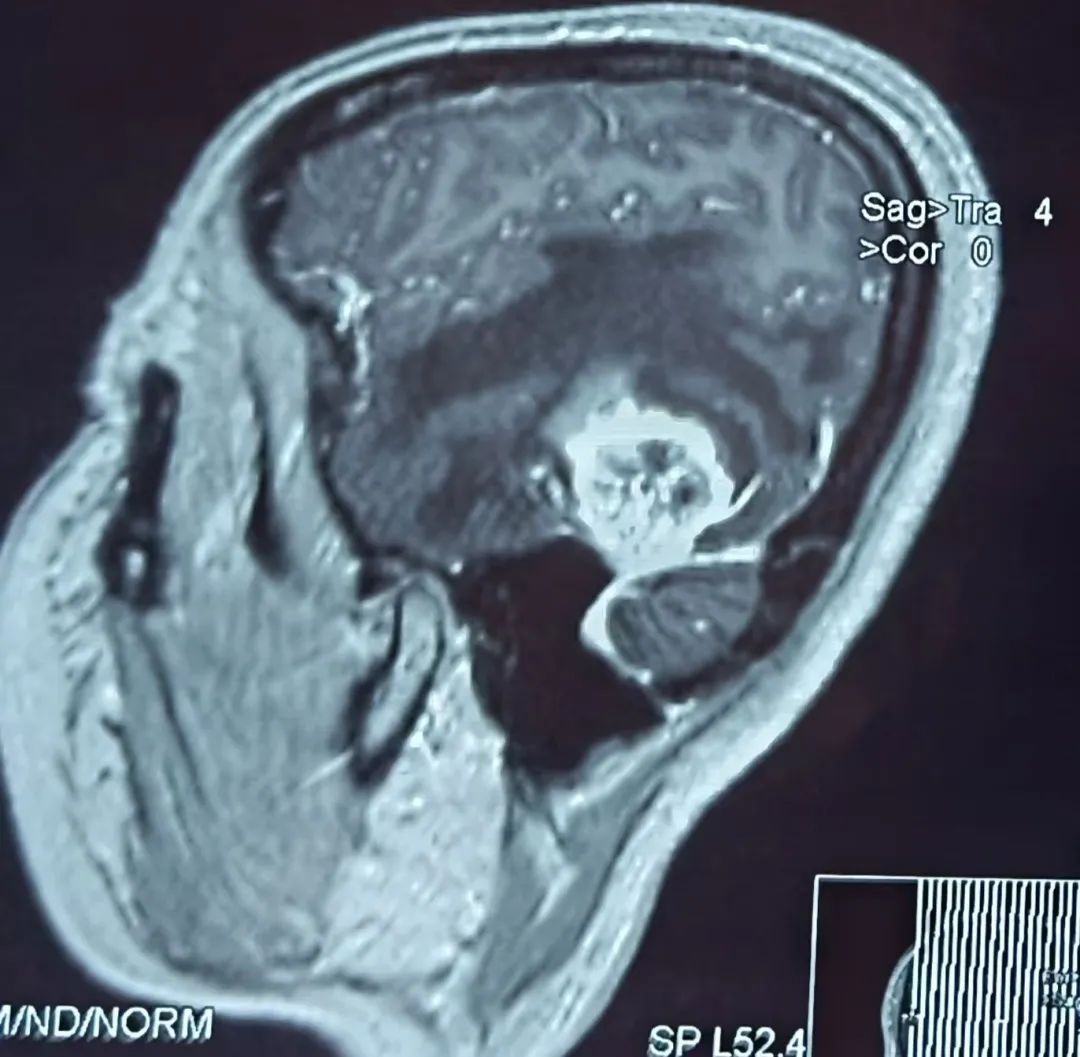

患者43歲,腎腫瘤術(shù)后一個(gè)半月開(kāi)始出現(xiàn)頭痛難忍,伴有惡心、嘔吐、言語(yǔ)不流利,每天靠止痛藥緩解頭痛,到醫(yī)院行頭部核磁檢查提示左顳葉占位,考慮腦轉(zhuǎn)移瘤可能性大。為進(jìn)一步診治,在朋友的介紹推薦下,患者來(lái)到我院神經(jīng)外科找到桑文淵主任。桑主任詳細(xì)詢(xún)問(wèn)病史,仔細(xì)閱片后,初步診斷患者為腦轉(zhuǎn)移瘤。

患者術(shù)前核磁影像

得知再患腫瘤,患者及家屬情緒極為低落。桑文淵主任給予耐心安撫溝通,表示頭痛、惡心、嘔吐、言語(yǔ)不流利這些癥狀都是腦轉(zhuǎn)移瘤顱內(nèi)壓增高造成的。通常腦轉(zhuǎn)移瘤周?chē)[嚴(yán)重,顱腔空間狹小,耐受力有限,如不積極手術(shù),隨著腫瘤不斷增大,水腫加重,隨時(shí)會(huì)有生命危險(xiǎn)?;颊吣X轉(zhuǎn)移瘤為單發(fā),具備手術(shù)指征,需要盡快手術(shù)切除,為后續(xù)綜合治療贏得時(shí)間?;颊呒覍倭私獠∏楹螅e極要求手術(shù)切除腦腫瘤。

患者入院后經(jīng)積極術(shù)前準(zhǔn)備,在麻醉科手術(shù)室的積極配合下,桑主任帶領(lǐng)神經(jīng)外科團(tuán)隊(duì)盡快為患者實(shí)施了左顳開(kāi)顱腫瘤切除術(shù),由于腫瘤位置較低較深,基底部位于顱底硬膜,部分與小腦幕緊密粘連,且腫瘤質(zhì)地較韌,血運(yùn)豐富,所以需要在顯微鏡下先離斷腫瘤基底部血運(yùn),才能減少術(shù)中出血。